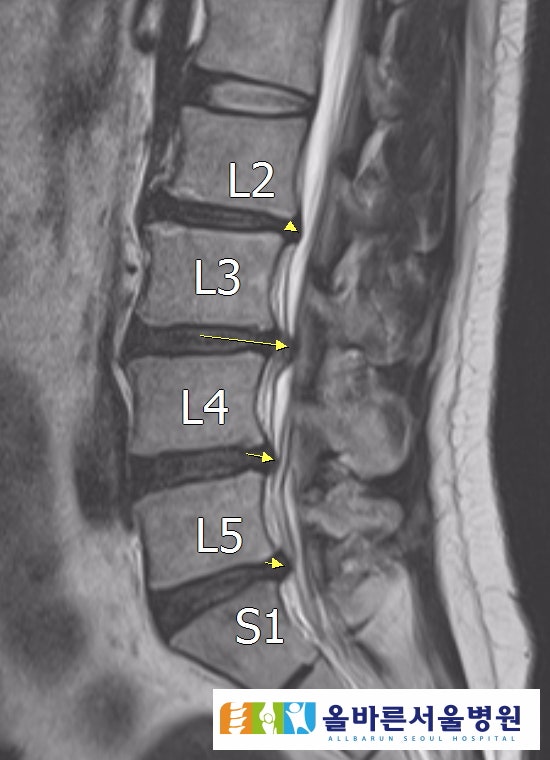

먼저 요추 추간판은 척추 사이에서 완충 역할을 하는 구조인데요! 특히 4번과 5번 요추 사이의 추간판과 5번과 1번 요추 사이의 추간판이 다른 추간판에 비해 가장 큰 충격을 받는다. 위치 때문에 대부분 요추 4-5번과 요추 5-천추 1번 추간판에서 발생합니다.

추간판의 구조는 콜라겐 섬유로 바깥쪽에는 섬유륜이라는 얇은 막이 있고 안쪽에는 수핵이라는 쫄깃한 핵이 있어 흐름이 끊어지면 추간판이 파열되는 경우가 많다. 이를 수핵 탈출증(HNP)이라고 합니다.